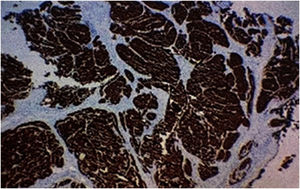

A biopsy of the skin lesion was performed and the histopathological study showed the dermis infiltrated by a malignant epithelial neoplasm of organoid pattern (Figs. 2 and 3). Immunohistochemistry showed reactivity with cytokeratin 40, 48, 50, and 50.6 in a Golgi pattern, chromogranin A and synaptophysin (Fig. 4) and was negative for TTF-1 and CK 20, characterizing it as a neuroendocrine tumor. The patient underwent computed tomography of the skull, thorax and total abdomen, which showed an extensively infiltrative pulmonary mass involving the main right bronchus, in addition to multiple lesions suggestive of brain, bone, liver, and adrenal metastasis. Bronchoscopy was performed, but the pulmonary mass biopsy was considered unfeasible due to heavy bleeding during the procedure.

The histopathological and immunohistochemical analyses help in the definitive diagnosis of carcinoid cutaneous metastases. There is dermal and sometimes subcutaneous infiltration by uniform tumor nests and sheets of cells, with hyperchromatic oval nuclei and scarce cytoplasm, showing immunoreactivity for neuroendocrine markers, including chromogranin, synaptophysin, and low molecular weight cytokeratin. The metastatic cells do not express CK5/6, CK7, CK20, and p63.2 The immunoexpression of TTF-1 and CDX2 may be useful in determining the primary site, as the former has shown high sensitivity and specificity for carcinoid tumors originating in the lung, whereas CDX2 expression is highly specific for tumors of gastrointestinal origin.2